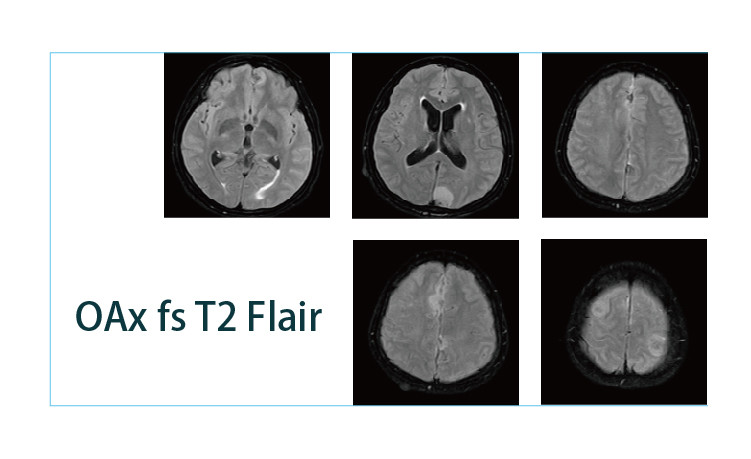

【朗润影像档案】20190419磁共振影像病例结果讨论